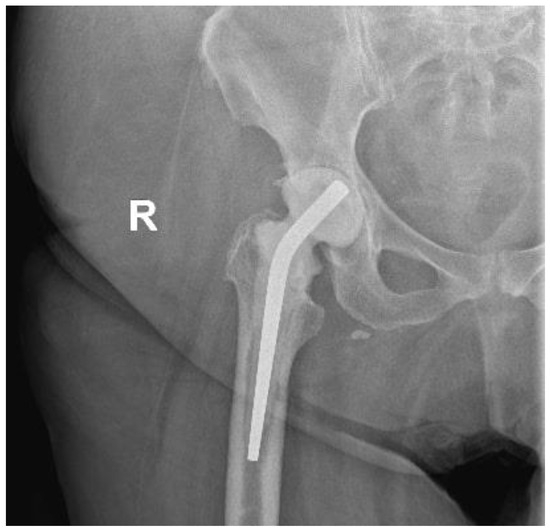

Susceptibility testing was conducted using gradient MIC test strips (Liofilchem, Italy) for the following antibiotics: benzylpenicillin, ciprofloxacin, clindamycin, daptomycin, linezolid, moxifloxacin, rifampicin and vancomycin, and by the disk diffusion method for ciprofloxacin, clindamycin and rifampicin. The isolate demonstrated susceptibility to linezolid, vancomycin and daptomycin but was resistant to benzylpenicillin, ciprofloxacin, clindamycin, rifampicin, moxifloxacin and tetracycline (EUCAST Clinical Breakpoints 2023). The minimum inhibitory concentration (MIC) value for daptomycin was 0.125 μg/mL (Figure 3).

Figure 3. Antibiogram based on the sonication fluid culture.